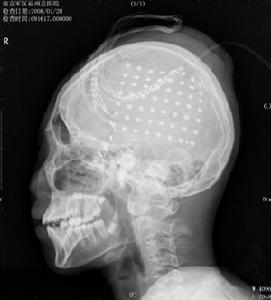

原發性癲癇避免誤診:腦囊蟲病可繼發癲癇發作,詳細詢問病史及查體,部分患者可見皮下、肌肉或眼內小結,病理檢查可發現囊蟲;血常規及腦脊液檢查可見嗜酸性細胞增多;囊蟲免疫診斷試驗其特異性抗體可為陽性;頭顱CT或MRI檢查可發現囊蟲病灶。